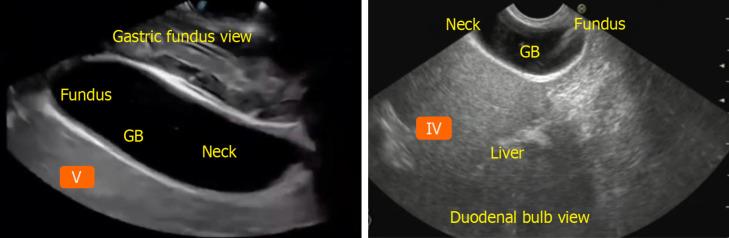

Owing to the complex and often asymptomatic presentations, the diagnosis of biliopancreatic diseases, including pancreatic and biliary malignancies, remains challenging. Recent technological advancements have remarkably improved the diagnostic accuracy and patient outcomes in these diseases. This review explores key advancements in diagnostic modalities, including biomarkers, imaging techniques, and artificial intelligence (AI)-based technologies. Biomarkers, such as cancer antigen 19-9, mutations, and inflammatory markers, provide crucial insights into disease progression and treatment responses. Advanced imaging modalities include enhanced computed tomography (CT), positron emission tomography-CT, magnetic resonance cholangiopancreatography, and endoscopic ultrasound. AI integration in imaging and pathology has enhanced diagnostic precision through deep learning algorithms that analyze medical images, automate routine diagnostic tasks, and provide predictive analytics for personalized treatment strategies. The applications of these technologies are diverse, ranging from early cancer detection to therapeutic guidance and real-time imaging. Biomarker-based liquid biopsies and AI-assisted imaging tools are essential for non-invasive diagnostics and individualized patient management. Furthermore, AI-driven models are transforming disease stratification, thus enhancing risk assessment and decision-making. Future studies should explore standardizing biomarker validation, improving AI-driven diagnostics, and expanding the accessibility of advanced imaging technologies in resource-limited settings. The continued development of non-invasive diagnostic techniques and precision medicine approaches is crucial for optimizing the detection and management of biliopancreatic diseases. Collaborative efforts between clinicians, researchers, and industry stakeholders will be pivotal in applying these advancements in clinical practice.